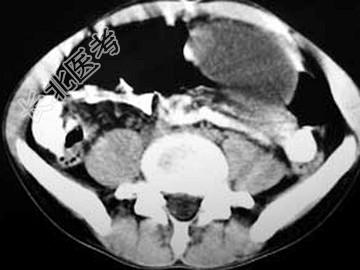

- 单项选择题男,33岁, 腹部外伤后2月余,腹部疼痛, 行CT扫描所见如图,最可能的诊断是 ( )

C、胰腺创伤性假性囊肿